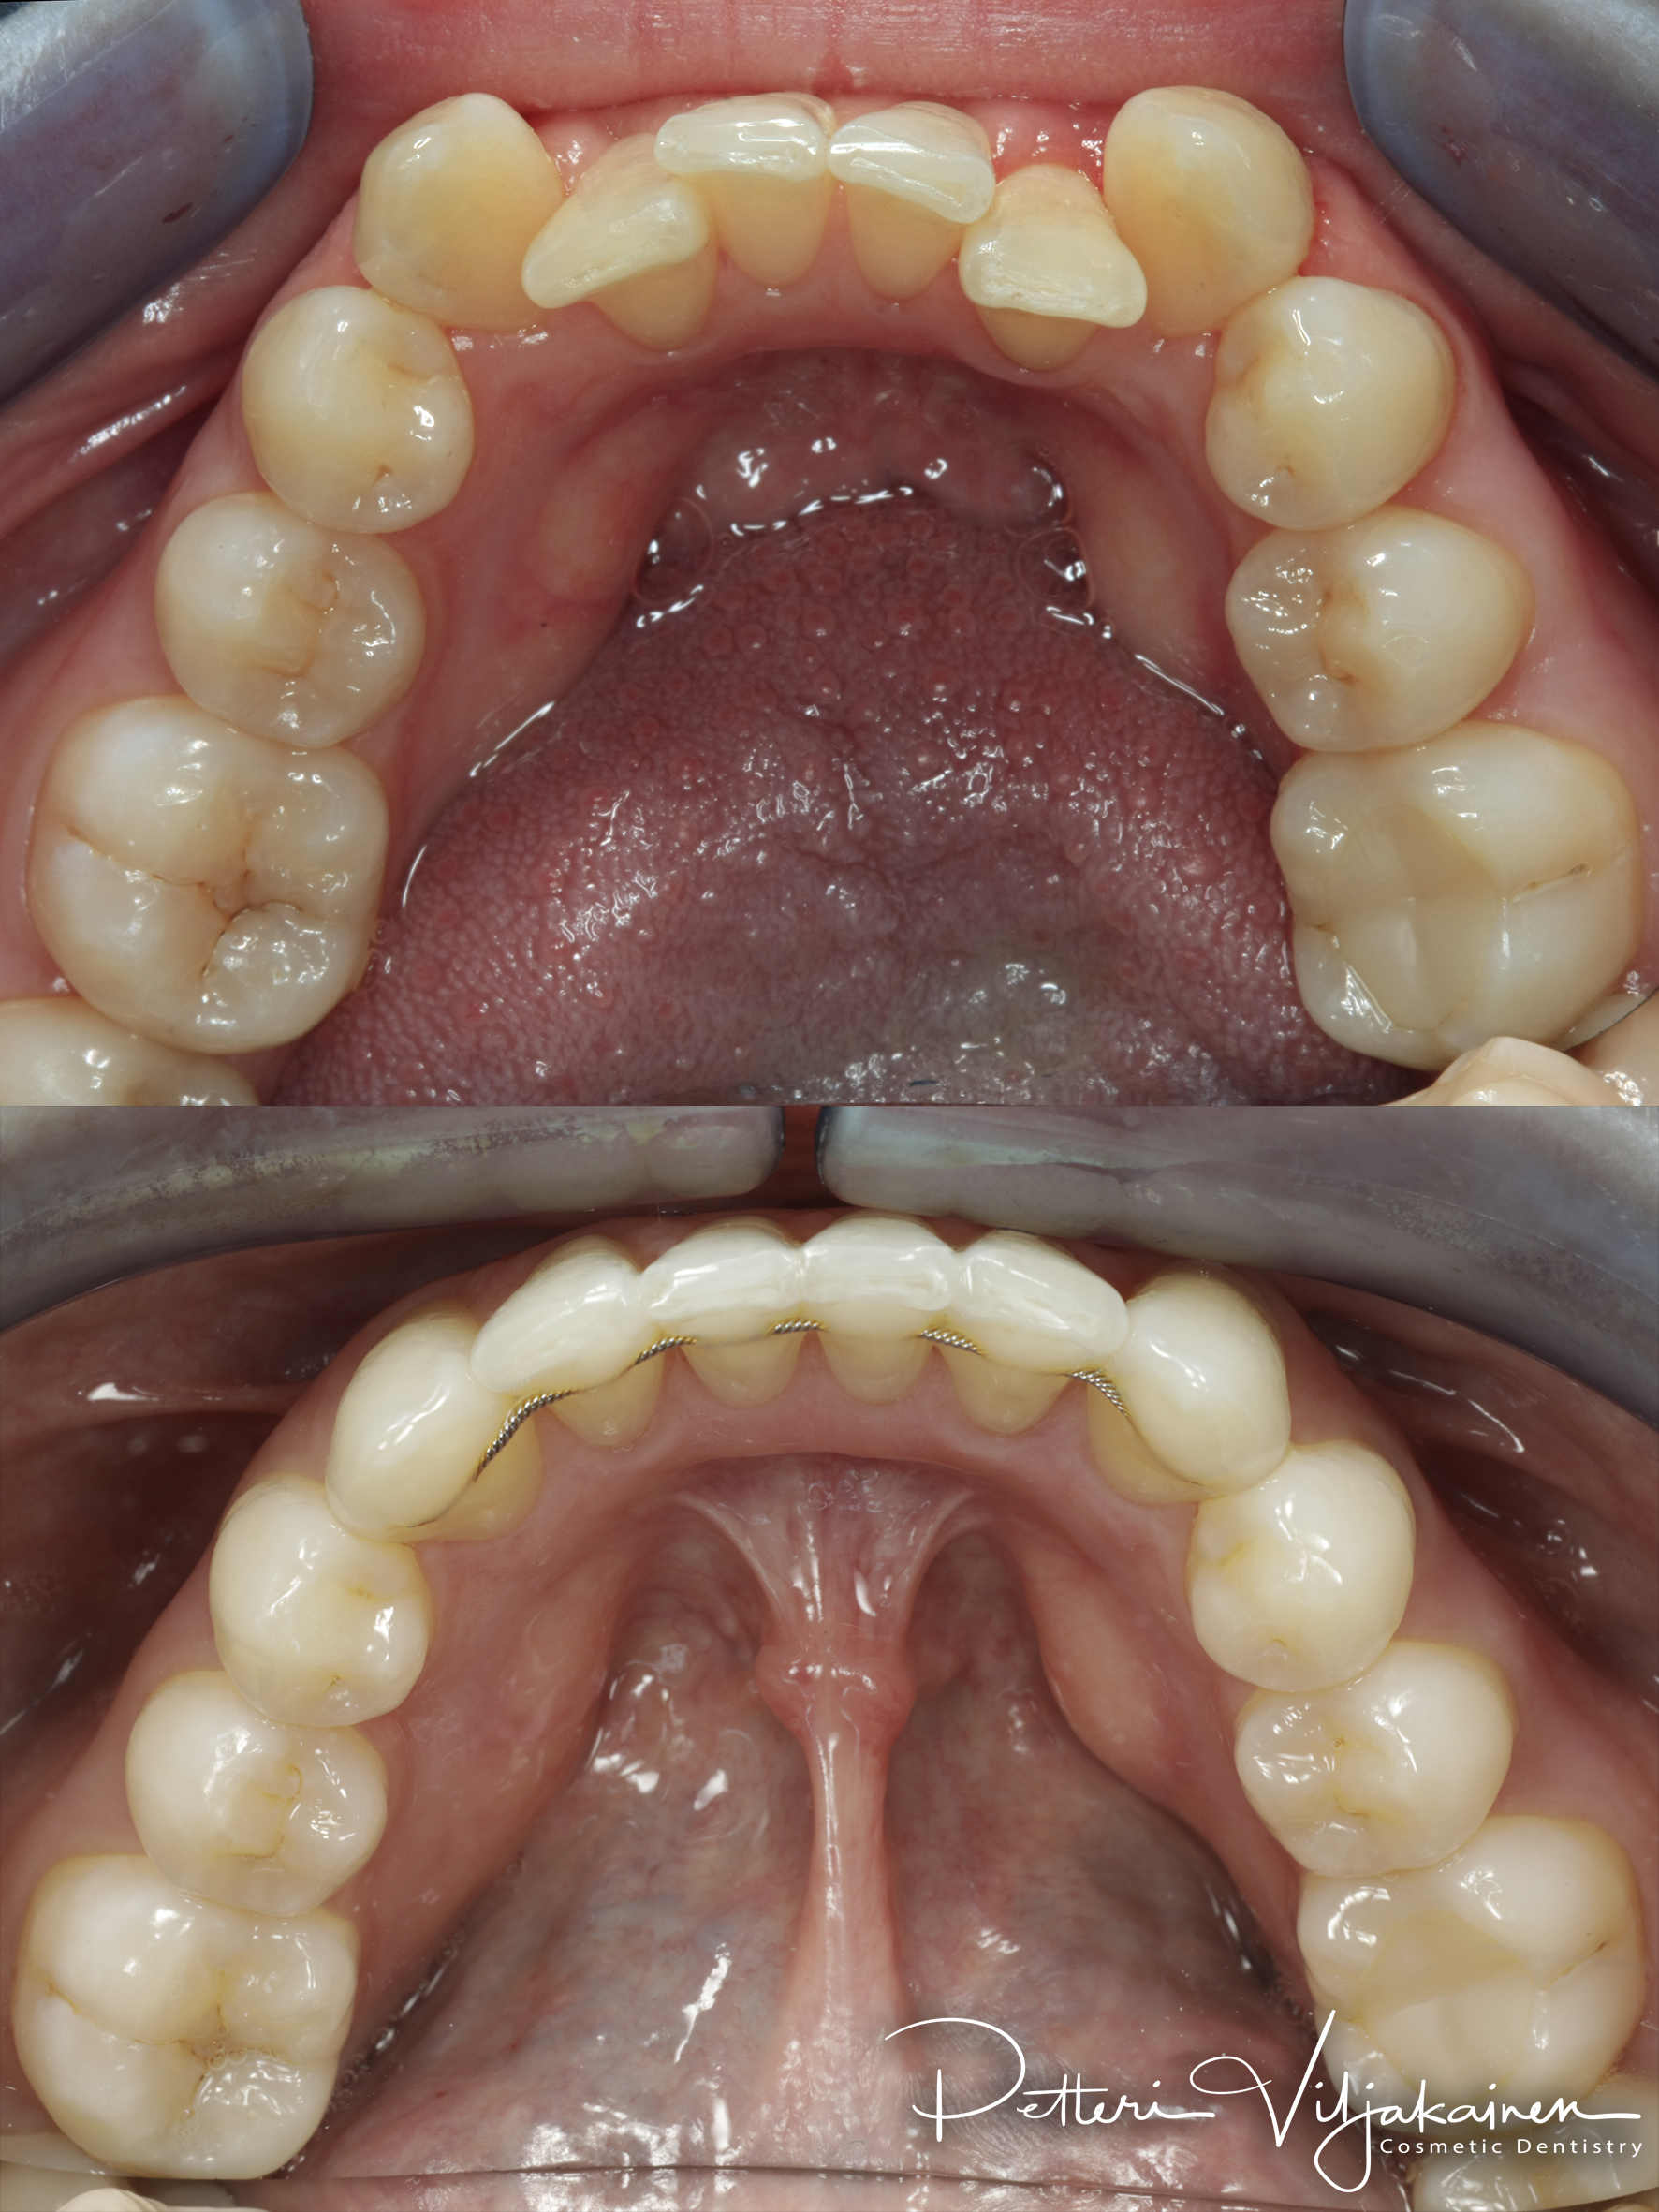

Retentio

Oikominen on aina retention eli lopputuloksen pysyvyyden kanssa koko loppuelämän hoito. Halusit tai et. Oikomisen jälkeen hampaat pyrkivät palautumaan takaisin kohti lähtötilannetta. Palautuminen on voimakkainta ensimmäisen vuoden aikana. Kaikkien oikomishoitojen jälkeen hampaat pitää "lukita" uusille paikoilleen hoitomenetelmästä tai iästä riippumatta. Valitettavan monelle potilaistani oikomista on tehty jo lapsuudessa, mutta koska lopputulosta ei lukittu aikoinaan mitenkään, esimerkiksi retentiolangoilla, palautuvat hampaat iän mukana jonkin verran tai pahimmassa tapauksessa kokonaan takaisin lähtöpisteeseen. Hampaisto ahtautuu luonnollisesti jonkin verran myös iästä johtuen.

Vaihtoehtoja retentioksi on kaksi: Joko hampaiden taakse pistetään kiinni ohut muotoon taivutettu metallilanka eli retentiolanka, tai öisin pidetään ohutta retentiokalvoa. Retentio valitaan sen perusteella kuinka paljon ja mihin suuntaan hampaita on liikutettu. Paras takuu on valiota molemmat jos purennassa on retentiolangalle tilaa.

Normaali käytäntö retentiolle on että alahampaiden taakse tuleee retentiolanka. Tämän lisäksi sekä ylä- että alahampaisiin tilataan lisäksi retentiokalvot eli Viverat. Ylähampaiden takana on purennassa niukalti tilaa eli sinne retentiolankaa ei aina saa mahtumaan.

Alla eri tyyppisiä retentiolankoja: